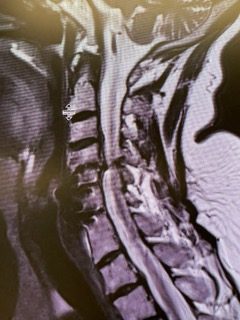

Revision Surgery Treats Intractable Neck Pain & Cervical Deformity

Author: Benjamin R. Cohen M.D., F.A.A.N.S., F.A.C.S., Read More!